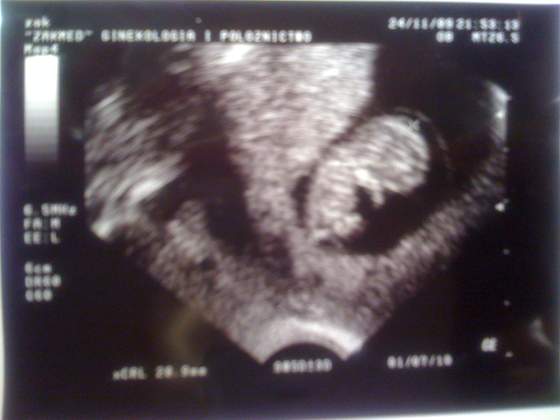

Nasze fasolki na USG

troche obrobilam fotke bo za duzo bylo juz na niej prywatnych danych

stopki troche niewyrazne, na usg lepiej widac